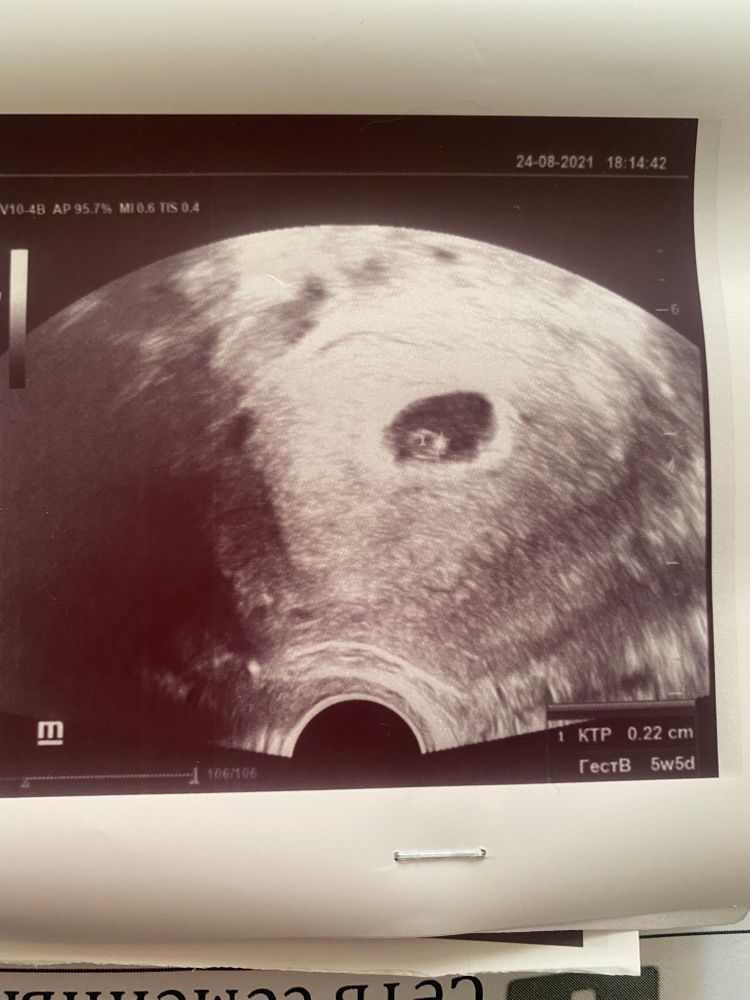

Сходила на узи,Чувствкю себя прекрасно,вообще признаков Б нет,но смущает маленький КТР

Gohi, я овуляцию чувствую,она была 19.08,но и по ней тоже 5 недель 5 дней не получается)

Gohi,вообще тогда ничего не понятно) если брать о 19.08 получается на 21 ДЦ,тогда сегодня 5 и 4 дня,почти как по узи 😂,а так конечно одному богу известно,когда это произошло)

Gohi, но судя по ктр не чувствуете вы Овуляцию 😆😆👍

У меня в 5Н 6Д ктр был 2 мм. Сейчас 13 недель, опережает на 4 дня